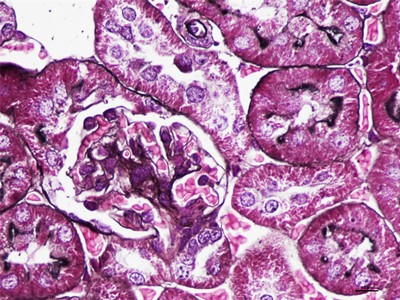

荧光全景扫描是对切片上的整个组织进行全景扫描,这样可充分证明切片实验结果,专用的计算机看图软件,可按不同倍率放大或缩小,无限连续变倍的观察切片内容,不失真,也可对数字切片进行多种方式标注并附加注释,及时标记需要的区域。以免记户可对数字切片进行传统性或者远程诊断等,并测量数字切片单个区域的长度、周长、面积等,荧光全景扫描也可对数字进行动态测量,实时拍照等,进一步观察仔细。

荧光全景扫描组织样本可实现1-400倍无限制连续倍增观察,针对于单个细胞可实现1-800倍无限制使用管理流程,成像速度快,一小时可扫描将近50多张常规病理性组织切片,占用时间空间小,扫描工作速度更快,图片高清晰的特点。